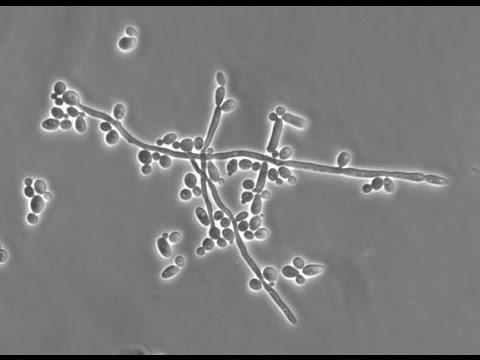

6/9/2021 4:40 PM 142979 20210609094032_kvasinky06.jpg